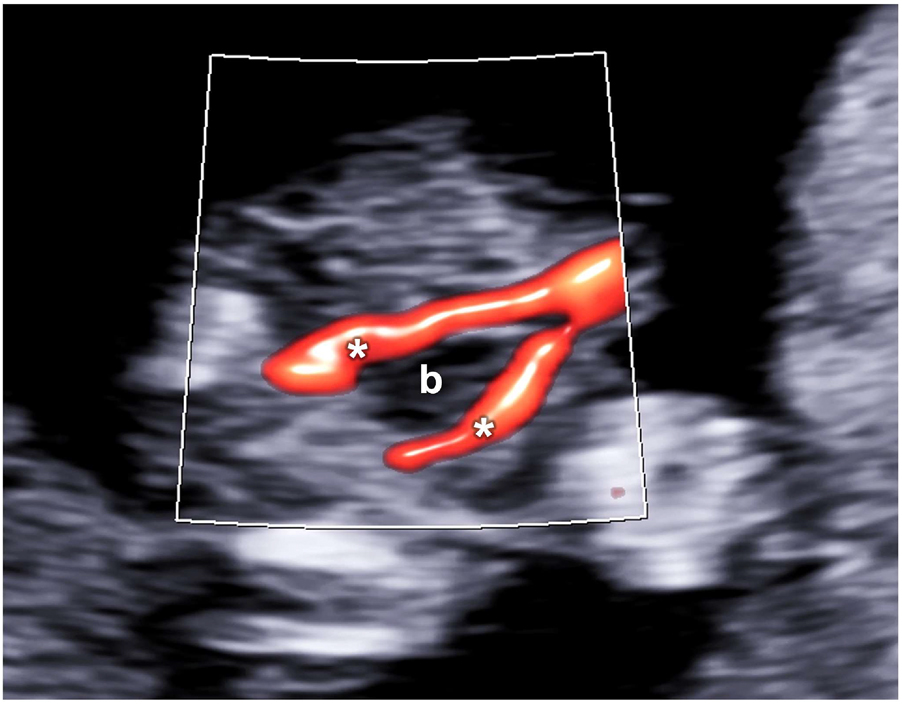

The fetal heart lies in the middle of the fetal chest, occupying about one third of it, with the apex pointing towards the left side and with two thirds of its area on the left of the thoracic midline. The four chambers should be balanced in size, with the ventricles mildly bigger than the atria (Figure 6). The great arteries are similar in size but showing opposite direction (crossover of the outflow tracts). The aorta arises from the left ventricle and points to the right and the pulmonary artery from the right ventricle but with an anteroposterior direction, roughly parallel to the midline. The aortic and ductal arches could be visualized just above the outflow tracts joining just before and to the left of the fetal spine (Figure 7). At the same level, the superior vena cava could be possibly visualized in the context of a “3 vessel and trachea” view.

Aortic (A) and ductal (D) arches (V-shape) highlighted by color Doppler on a three vessels and trachea view.

The aortic arch is on the left of the trachea (T). Superior vena cava (C) is just on the right of the aorta (A).

The visualization of the three-vessels or arches view (V-sign) on the axial plane by color Doppler is suggested but not mandatory in the first trimester.

The plane, including the arches, could be obtained starting from the four chambers apical view, sweeping the probe cranially. Such structures could be highlighted by color Doppler, which would appear similar in size and color in normal conditions.